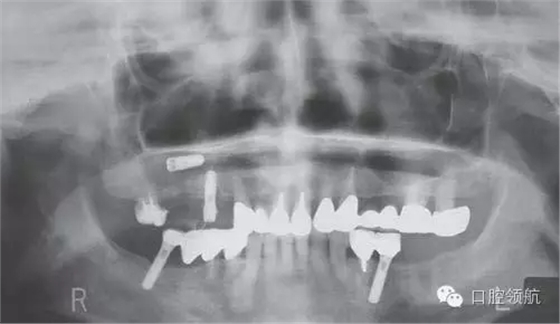

在外院進(jìn)行上頜竇提升術(shù)7~8個(gè)月后,二次手術(shù)時(shí)發(fā)現(xiàn)種植體松動(dòng),在去除種植體時(shí)發(fā)生種植體進(jìn)入上頜竇的情況。被介紹來(lái)我院就診,于當(dāng)日進(jìn)行了進(jìn)入竇種植體的去除術(shù)(圖1、圖2)。

圖1 來(lái)院時(shí)的曲面斷層影像。